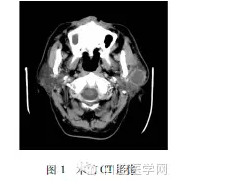

入院初步診斷:腮腺區(qū)囊腫伴出血。入院后完善相關(guān)檢查檢驗(yàn),行腮腺螺旋CT平掃+增強(qiáng),結(jié)果回報:左側(cè)腮腺可見類圓形軟組織密度影,密度均勻,邊界清楚,增強(qiáng)掃描后病灶不均勻強(qiáng)化,邊緣強(qiáng)化明顯(圖1)。

EHE有沿解剖位置如血管、神經(jīng)及筋膜等造成局部侵犯的傾向。本例患者臨床亦表現(xiàn)為單發(fā)于左腮腺的密度不均的包塊,伴有疼痛腫脹不適,復(fù)發(fā)后查體發(fā)現(xiàn)腫瘤沿周邊皮下組織侵襲蔓延。EHE在CT和MRI檢查中為單發(fā)性或多發(fā)性結(jié)節(jié),通常低密度影,內(nèi)部結(jié)構(gòu)不均勻,可有液化或鈣化形成,增強(qiáng)掃描后可見強(qiáng)化,此患者的入院CT及MRI表現(xiàn)與既往文獻(xiàn)資料中的EHE的影像學(xué)表現(xiàn)描述一致。